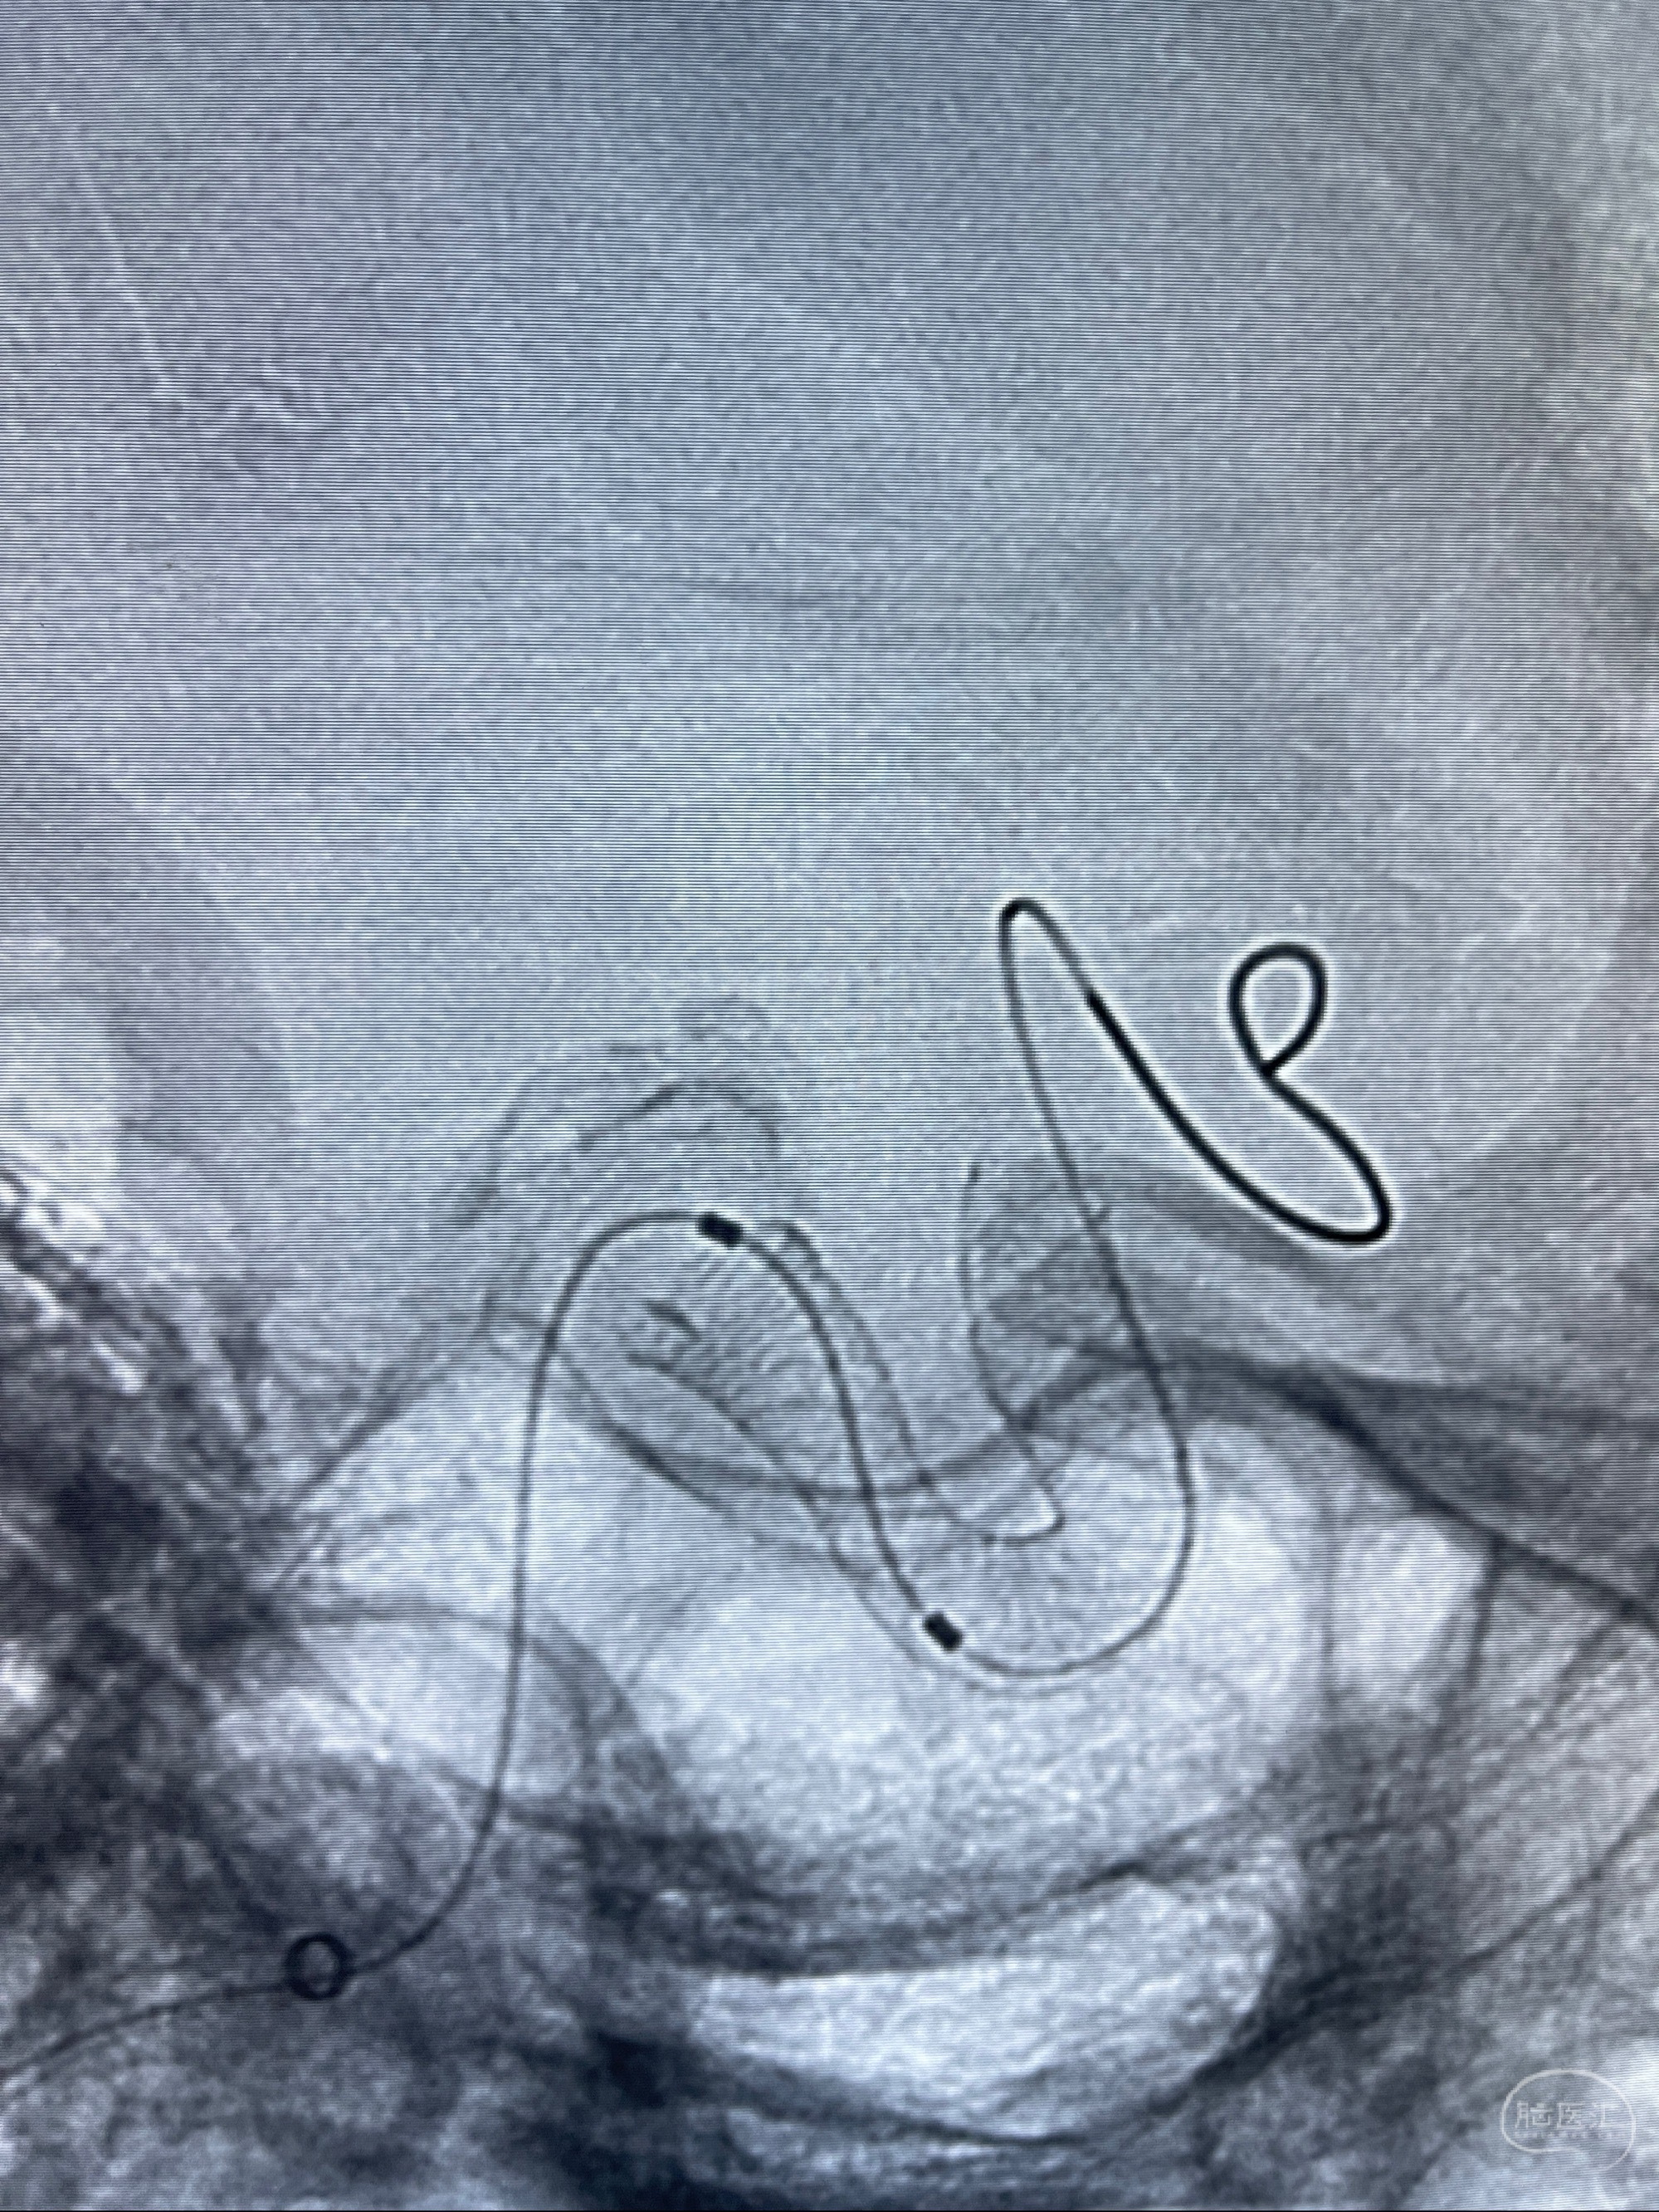

2023-08-01全麻下行双侧颈眼动脉瘤支架辅助栓塞

- pipeling4.5-20mm

- pipeline 4.0-20mm

手术顺利,麻醉苏醒佳,遵嘱动作